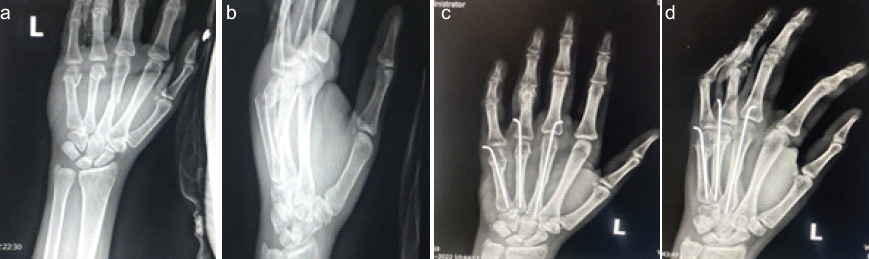

Patient in supine, with affected limb in arm table, parts painted and draped. Retrograde K-wire technique was used. A skin incision of size 0.5 cm was made over the dorsal aspect of metacarpophalangeal (MCP) joint. Extensor tendons incised and retracted medially and laterally. A 1.5 mm K-wire was selected and inserted over the dorsal aspect of the metacarpal head after closed reduction of the fracture by traction and digital manipulation under fluoroscopic guidance. With fracture in reduction, K-wire was passed across the fracture site up to the base of the metacarpal. Protruding K-wire was bent and cut externally (Fig. 1a, b, c, d).

Figure 1: (a and b) Pre-operative X-ray left hand showing # of 3rd, 4th, 5th metacarpals, and (c and d) Post-operative X-ray after K-wire fixation.